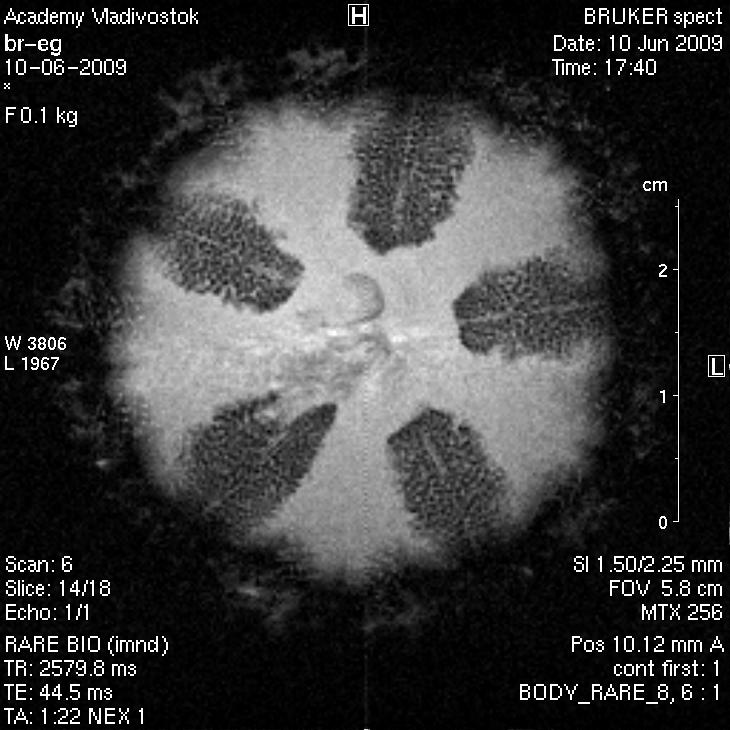

На фото МРТ изображение морского ежа. Сделанное на томографе Bruker Pharmascen 7 T.